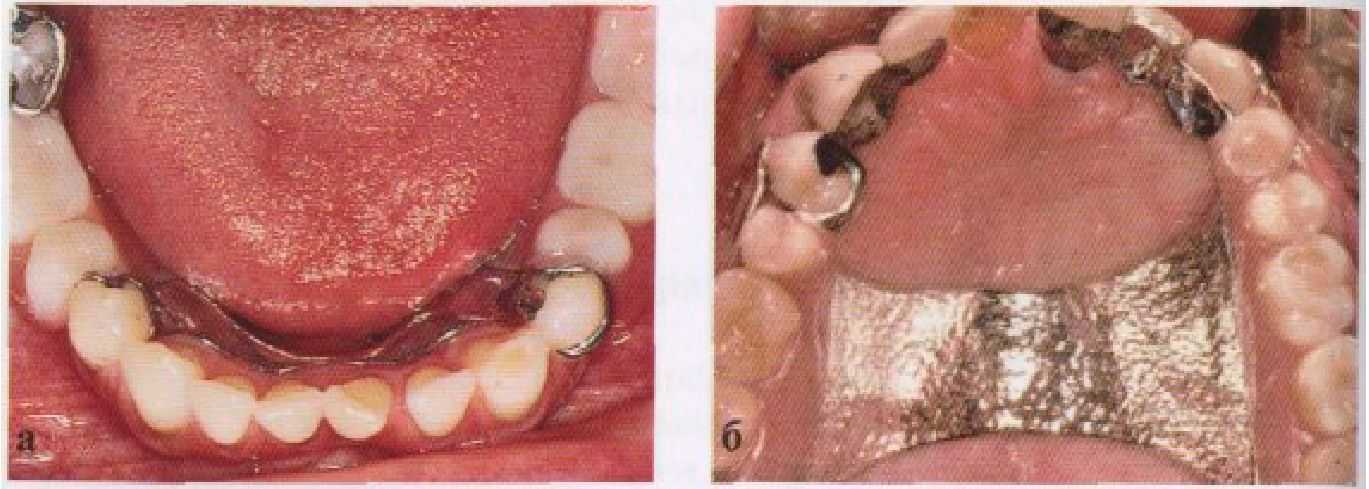

Рис 3-10 Примеры частичных съемных протезов: (а) на верхней и (б) на нижней челюсти где элементы протеза расположены таким образом, чтобы оставить свободным десневой край. (С разрешения проф. В, 0*al 1.)